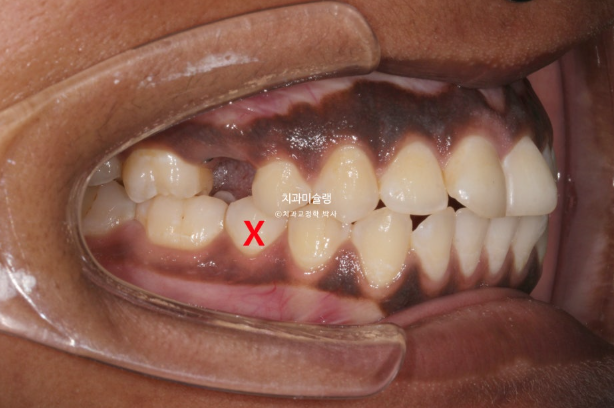

The patient had previously undergone non-extraction orthodontic treatment but did not wear retainers, resulting in relapse of the anterior teeth. Due to dental caries, several teeth were subsequently lost, leading the patient to seek re-treatment.

In the maxilla, one premolar had decayed to the point where only the root remained.

In the mandible, a molar was in a similar condition, with only the root remaining.

In cases where a premolar is missing like this, if protrusion or crowding is present, we can proceed as if premolar extraction had already been performed. By extracting other compromised premolars and utilizing the extraction spaces, we can resolve crowding and protrusion simultaneously. This approach is advantageous, as premolar extraction is often indicated in such cases, and it eliminates the need for implants.